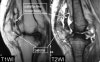

MRI에서는 **radiolucent body도 발견할 수 있습니다.

MRI : Loose body